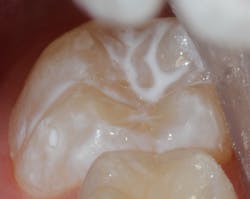

Sealant placement techniques should include complete isolation and an intermediary bonding layer (figure 1).25–29 The bonding layer and sealant curing can be one of two different methods: either placement and light-curing simultaneously in a simplified sealant technique or separately. Evidence-based studies show results favoring the individual light-curing technique in cases where conditions are dry and noncontaminated. In cases where there is saliva contamination, bond strength was the same in either simultaneous or individual light-cure placement methods.30–31